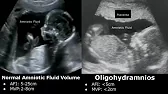

Amniotic Fluid Volume Ultrasound Normal Vs Abnormal | Oligohydramnios/Polyhydramnios | AFP/MVP USG

Dr. Sam’s Imaging Library24